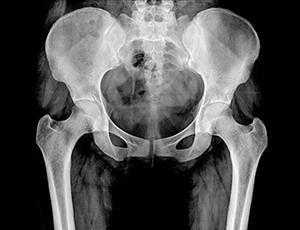

Рентген костей таза и тазобедренных суставов может проводиться в трех проекциях: переднезадней (ПЗ), заднепередней (ЗП) и латеральной (боковой). На снимке спереди видны тазовые кости от верхней части гребня подвздошной кости до проксимального отдела диафиза бедренной кости, лобковая и седалищная кости, тазобедренный сустав, запирательные отверстия, большие вертелы проксимального отдела бедра в профиль.

На снимке сбоку визуализируется крестец, копчик, пояснично-крестцовый переход, наложенные друг на друга бедренные кости и верхняя часть бедра.

Визуализируя гребень подвздошной кости, крестец, подвздошно-крестцовые сочленения, большое тазовое кольцо, лобковую и седалищную кости, проксимальный отдел бедра, рентген таза может показать: анатомические нарушение формы таза или тазобедренного сустава; переломы таза; перелом, вывих или артрит тазобедренного сустава; опухоли костей таза (остеосаркомы).

Показатели нормы

На снимке рентгенограммы должно проявиться симметричное изображение двух половин таза, крестца, межпозвонковых отверстий крестца, а также ветвей лобковых костей и седалищных. Должно отчётливо просматриваться вещество кости, виднеться контуры двух вертлужных впадин и шейки бедренных костей.

Существуют определенные показатели нормы состояния и строения тазобедренного сустава, с которыми при расшифровке сопоставляются фактические данные. Например, угол Виберга в норме должен располагаться между линией центра головки бедра, верхне-наружным краем вертлужной впадины. Нормальная величина угла составляет примерно 30 градусов. Угол наклона входа в вертлужную впадину также имеет норму - 31-42 градуса. Угол шеечно-диафизарный в норме должен быть от 115 до 140 градусов.